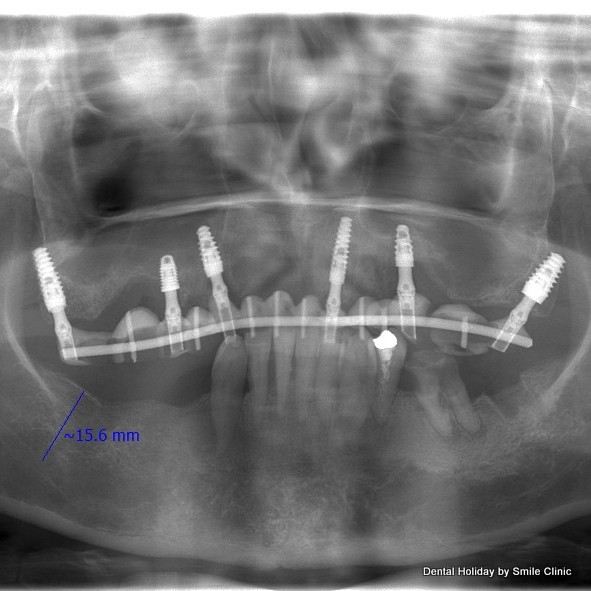

Upper teeth – removable denture was replaced for a fixed bridge fitted on dental implants.

Dr Marek first fitted dental implants for the upper jaw, and then a temporary bridge was fitted.

Bottom teeth were very loose, and a tooth extraction had to be done because severe gum disease called periodontal disease loosened the teeth by damaging the bone around them

Extraction of lower teeth and Lower dental implants were placed at the second visit.